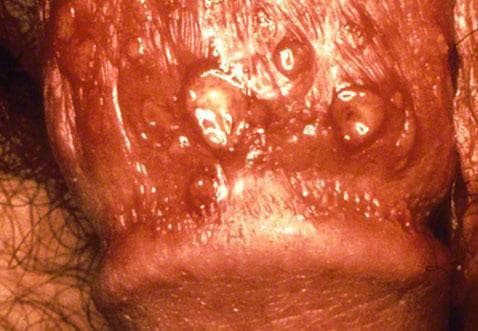

Shortly after these initial symptoms appear, small lesions will appear in and around the genitals and rectum. They start as small red bumps that appear in the genitalia and rectum that feel itchy and painful. They soon become fluid-filled blisters that break and ooze.

Finally, the blisters begin to heal after a couple of days but sometimes can take up to 2 - 4 weeks in initial outbreaks. The sores will scab and crust over, although they may break and bleed.

A genital herpes sore can look like several conditions such as jock itch, ingrown hairs, razor burn or genital warts. Please refer to the slides below to help distinguish from other conditions and see what genital herpes looks like.

Please note: images are explicit in nature